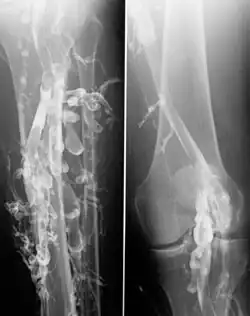

Die Diagnose einer Venenthrombose wird heute üblicherweise mittels Sonographie (Doppler- und Duplex-Sonographie) gestellt. Falls dieser nicht vorhanden ist oder nach der Ultraschalluntersuchung weiter Unklarheiten über das weitere Vorgehen bestehen, kommt die Phlebographie (Röntgenuntersuchung mit Kontrastmittel) zur Anwendung. Ist ein modernes Ultraschallgerät vorhanden und ist der Untersucher ausreichend erfahren, muss die aufwändigere und den Patienten belastendere Phlebographie nur noch selten zum Einsatz kommen.